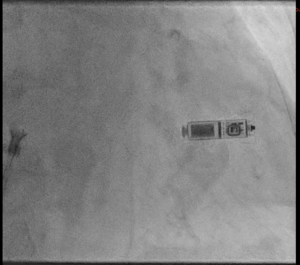

Als Alternative steht in bestimmten Situationen der sogenannte „Elektrodenlose Schrittmacher“ zur Verfügung. Hierbei wird eine kleine Schrittmacher“kapsel“ direkt über die Vene in der Leiste in die rechte Herzkammer implantiert. Dieses System kommt entsprechend ohne eigentliches „Aggregat“ und ohne Elektroden aus (Abb. 3). In einer individuellen Analyse beurteilen wir, für welche Patienten welches System am besten in Frage kommt.

Abb 3

Der Herzschrittmacher wird unter Lokalanästhesie in einer knapp einstündigen Operation unter die Haut implantiert. Die Elektroden wird durch einen kleinen Hautschnitt in eine Vene eingeführt und zum Herzen vorgeschoben. Unter Röntgenkontrolle wird diese in der Herzkammern verankert. Über die Elektrode werden elektrische Impulse abgegeben, welche das Herz stimulieren, damit es nicht zu langsam schlägt. Der individuell programmierbare Schrittmacher wird in der Regel 1-2x / Jahr kontrolliert.

Als Alternative steht in bestimmten Situationen der sogenannte „Elektrodenlose Schrittmacher“ zur Verfügung. Hierbei wird eine kleine Schrittmacher“kapsel“ direkt über die Vene in der Leiste in die rechte Herzkammer implantiert. Dieses System kommt entsprechend ohne eigentliches „Aggregat“ und ohne Elektroden aus (Abb. 3). In einer individuellen Analyse beurteilen wir, für welche Patienten welches System am besten in Frage kommt.

Abb 3